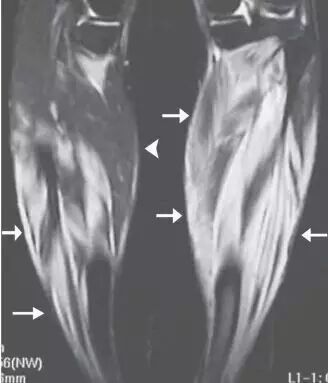

![]()

图8.26岁女性多发性肌炎,呈现双侧下肢疼痛和肌肉无力。(a)大腿的轴向T2加权的MR图像显示在股外侧肌,中间肌,内侧肌和股直肌(箭头)的异常,广泛的羽状水肿。注意保持正常的肌肉结构。T1加权成像(未显示)在受影响的肌肉中未显示信号改变或萎缩,或在此情况下有助于诊断。(b)两腿的冠状动脉脂肪抑制的T2加权的MR图像还在小腿的肌肉(箭头)中显示广泛的水肿信号。右腓肠肌的内侧头显得幸免(箭头)。